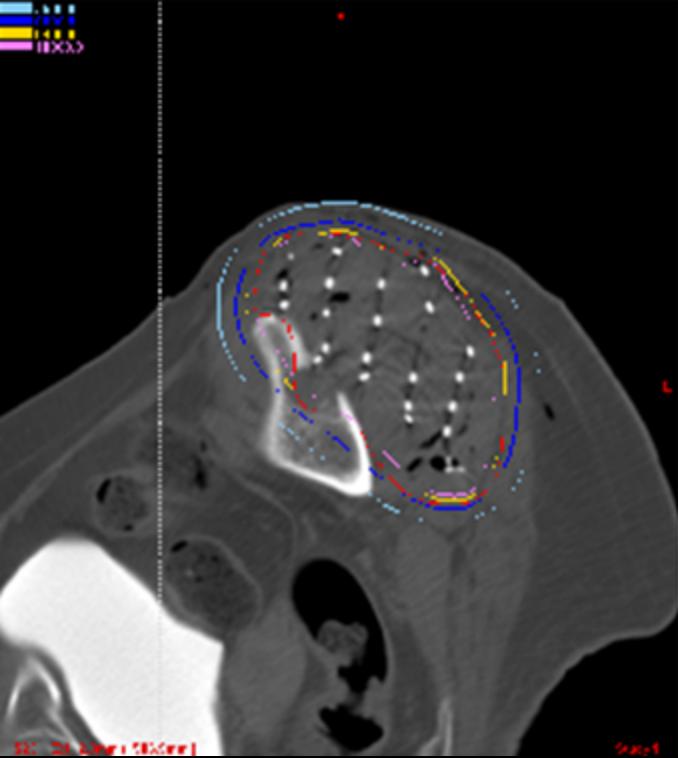

2024年1月16日,肿瘤放疗科顺利完成二附院首例CT引导联合共面模板辅助放射性I-125粒子植入术,预示着肿瘤放疗科介入放射治疗室正式开启。

该患者为纤维肉瘤晚期,既往多程化疗且已经过外放疗,经外科评估无手术指征,经马红兵主任及王宝峰教授会诊后,为患者提出放射性I-125粒子植入治疗。该例粒子植入术由肿瘤放疗科马红兵主任全程指导及质控,许雅琼护士长精心筹备,潘继元技术员精准定位及制作体膜,郭昱言医师、赵茜茜医师、崔颖涛护师、李宾进修医师等肿瘤放疗科医师共同参与完成。患者手术全程无痛苦,术后各项指标无异常,术后第二天顺利出院。

肿瘤放疗科3D打印共面/非共面模板及导航系统的联合应用,结合术前、术中、术后TPS计划验证,将为我院放射性粒子植入治疗的规范化开展、治疗精度和患者局控率的提高及该技术的推广起到积极的推进作用。